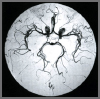

carotid artery disease

Although there are no symptoms specific to carotid artery disease. The warning signs of a stroke are a good way to tell if there is a blockage in the carotid arteries. Transient Ischemic Attack CT., is one of the most important warring signs that you may soon have a stroke. Sometimes called "mini-strokes," TIAs are temporary episodes of headache. Dizziness, tingling, numbness, blurred vision, confusion, or paralysis that can last anywhere from a few minutes to a couple of hours. See a doctor right away if you or someone you know has the symptoms of a TIA.